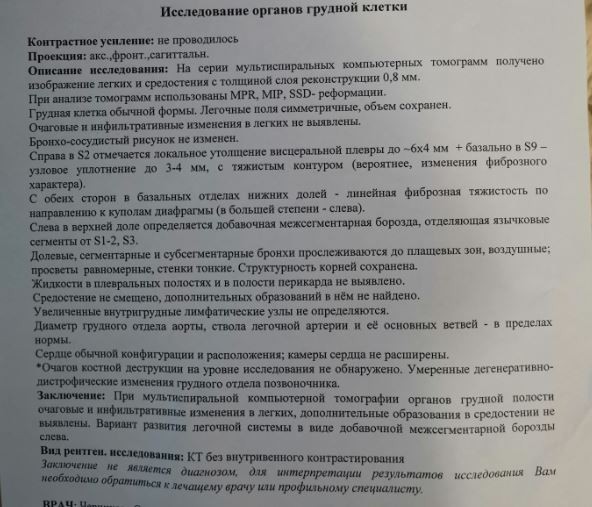

Фотографии и снимки КТ легких без контрастных веществ

Раздел: Визуальный дайджест